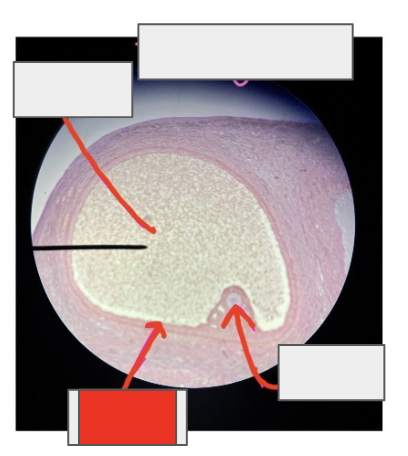

ovary

What organ is this from?

Tertiary follicle

what is this whole thing?

Primary oocyte

Granulosa cells

Antrum